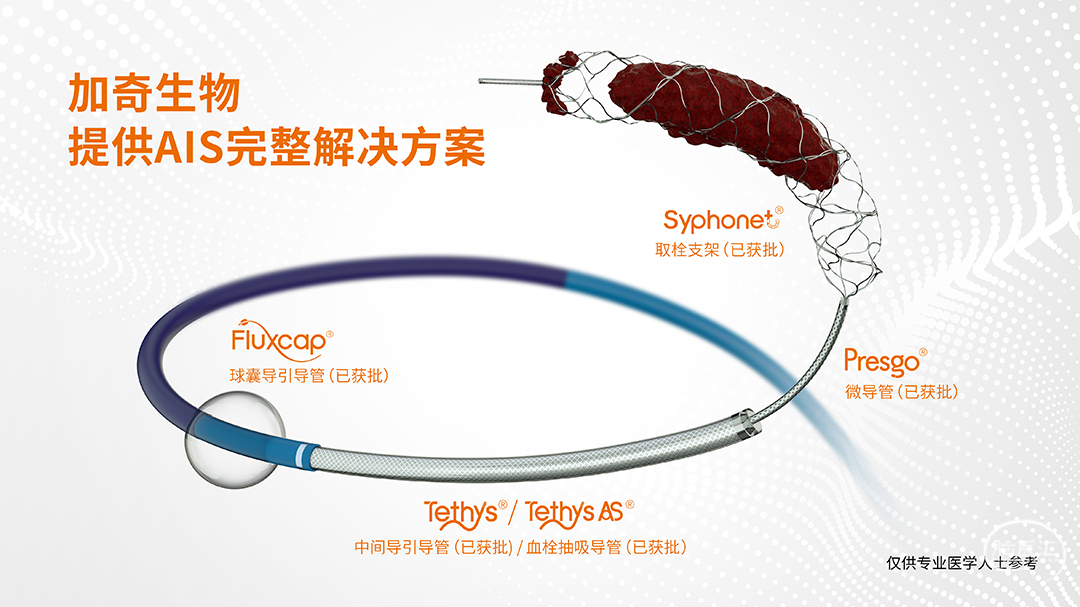

手术器械

8F 动脉鞘

6F 80cm 长鞘

6F 125cm 中间导管

200cm、300cm 0.014inch 微导丝

Headway17微导管

加奇生物 SacSpeed®球囊扩张导管 1.5×15mm

加奇生物 Syphonet®取栓支架 3×25mm

加奇生物 Fastunnel®输送型球囊扩张导管 1.75×15mm

自膨式闭环支架 4×16mm

在Syphonet®取栓支架 3×25mm远端保护下行BASIS技术,SacSpeed®球囊扩张导管 1.5×15mm扩张后造影。

Fastunnel®输送型球囊扩张导管 1.75×15mm球囊再次扩张,置入自膨式闭环支架置入后造影。